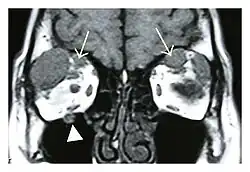

Right optic disc lesion in IgG4-ROD

Mass lesion around the right optic disc in a 44-year-old man with IgG4-related ophthalmic disease and a serum IgG4 of 599 mg/dL.[1] (T2-weighted MRI)